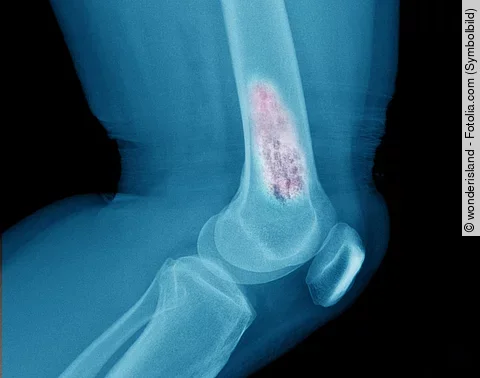

KnochenkrebsDie Schwäche des Tumors

LMU-Forscher zeigen, dass das Ewing-Sarkom in einen speziellen Signalweg in der Knochenentwicklung eingreift und sich damit angreifbar macht. Dies könnte vor allem bei hochaggressiven Tumoren neue therapeutische Möglichkeiten eröffnen.